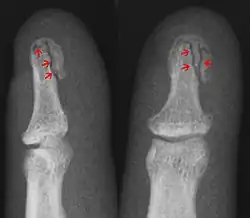

In the fingertip. More images

Avulsion fracture A fragment of bone is separated from the main mass (image shows a Busch fracture)